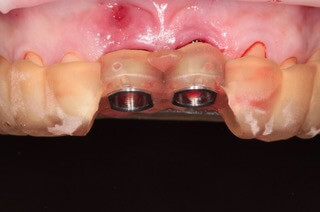

V ďalšom kroku sme virtuálne vložili implantáty v správnej protetickej polohe, navrhli šablónu pre ich zavedenie, namodelovali individuálne abutmenty a korunky. Kompletné dáta sme exportovali pre frézovanie a 3D tlač. V laboratóriu sa pomocou 3D tlačiarne vytlačila chirurgická šablóna, ktorá nám slúži na presné zavedenie implantátov – použili sme implantačný systém Dentium Super Line. Následne boli vyfrézované zirkonové abutmenty a plastové dočasné korunky.

Ukážka - navigovaná chirurgia z praxe